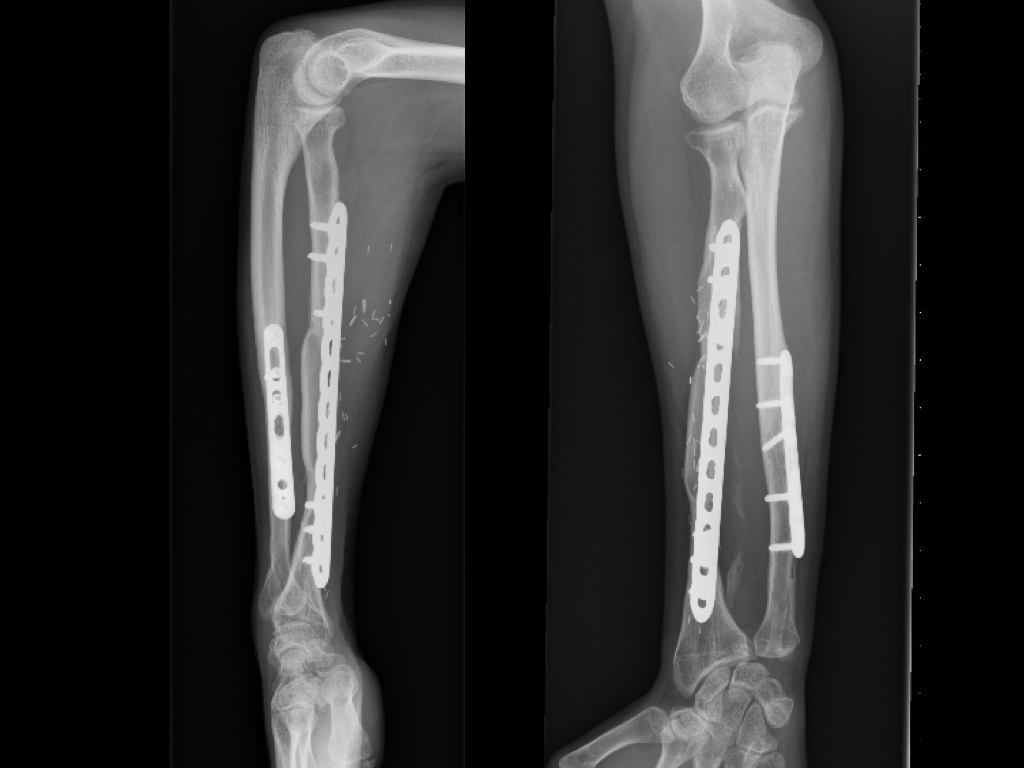

Experiencia inicial en un centro de alta complejidad con el injerto vascularizado de peroné en defectos óseos segmentarios del miembro superior. [Early experience in a high complexity Hospital with the vascularized fibular graft in segmental bone defects of the upper limb.]